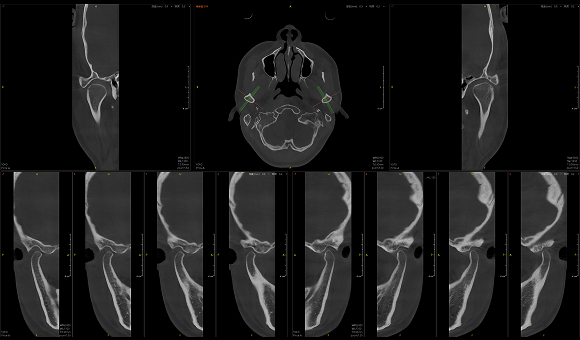

Pirox-A的小视野超清模式,采用旋转阳极射源成像。旋转阳极射源的亮度更高,焦点尺寸可以达到惊人的0.3mm,让Pirox-A可轻松捕捉细微玄妙之处。此外,旋转阳极通过不断旋转,可以大大增加散热面积,降低球管热累积进而提升连续工作能力。